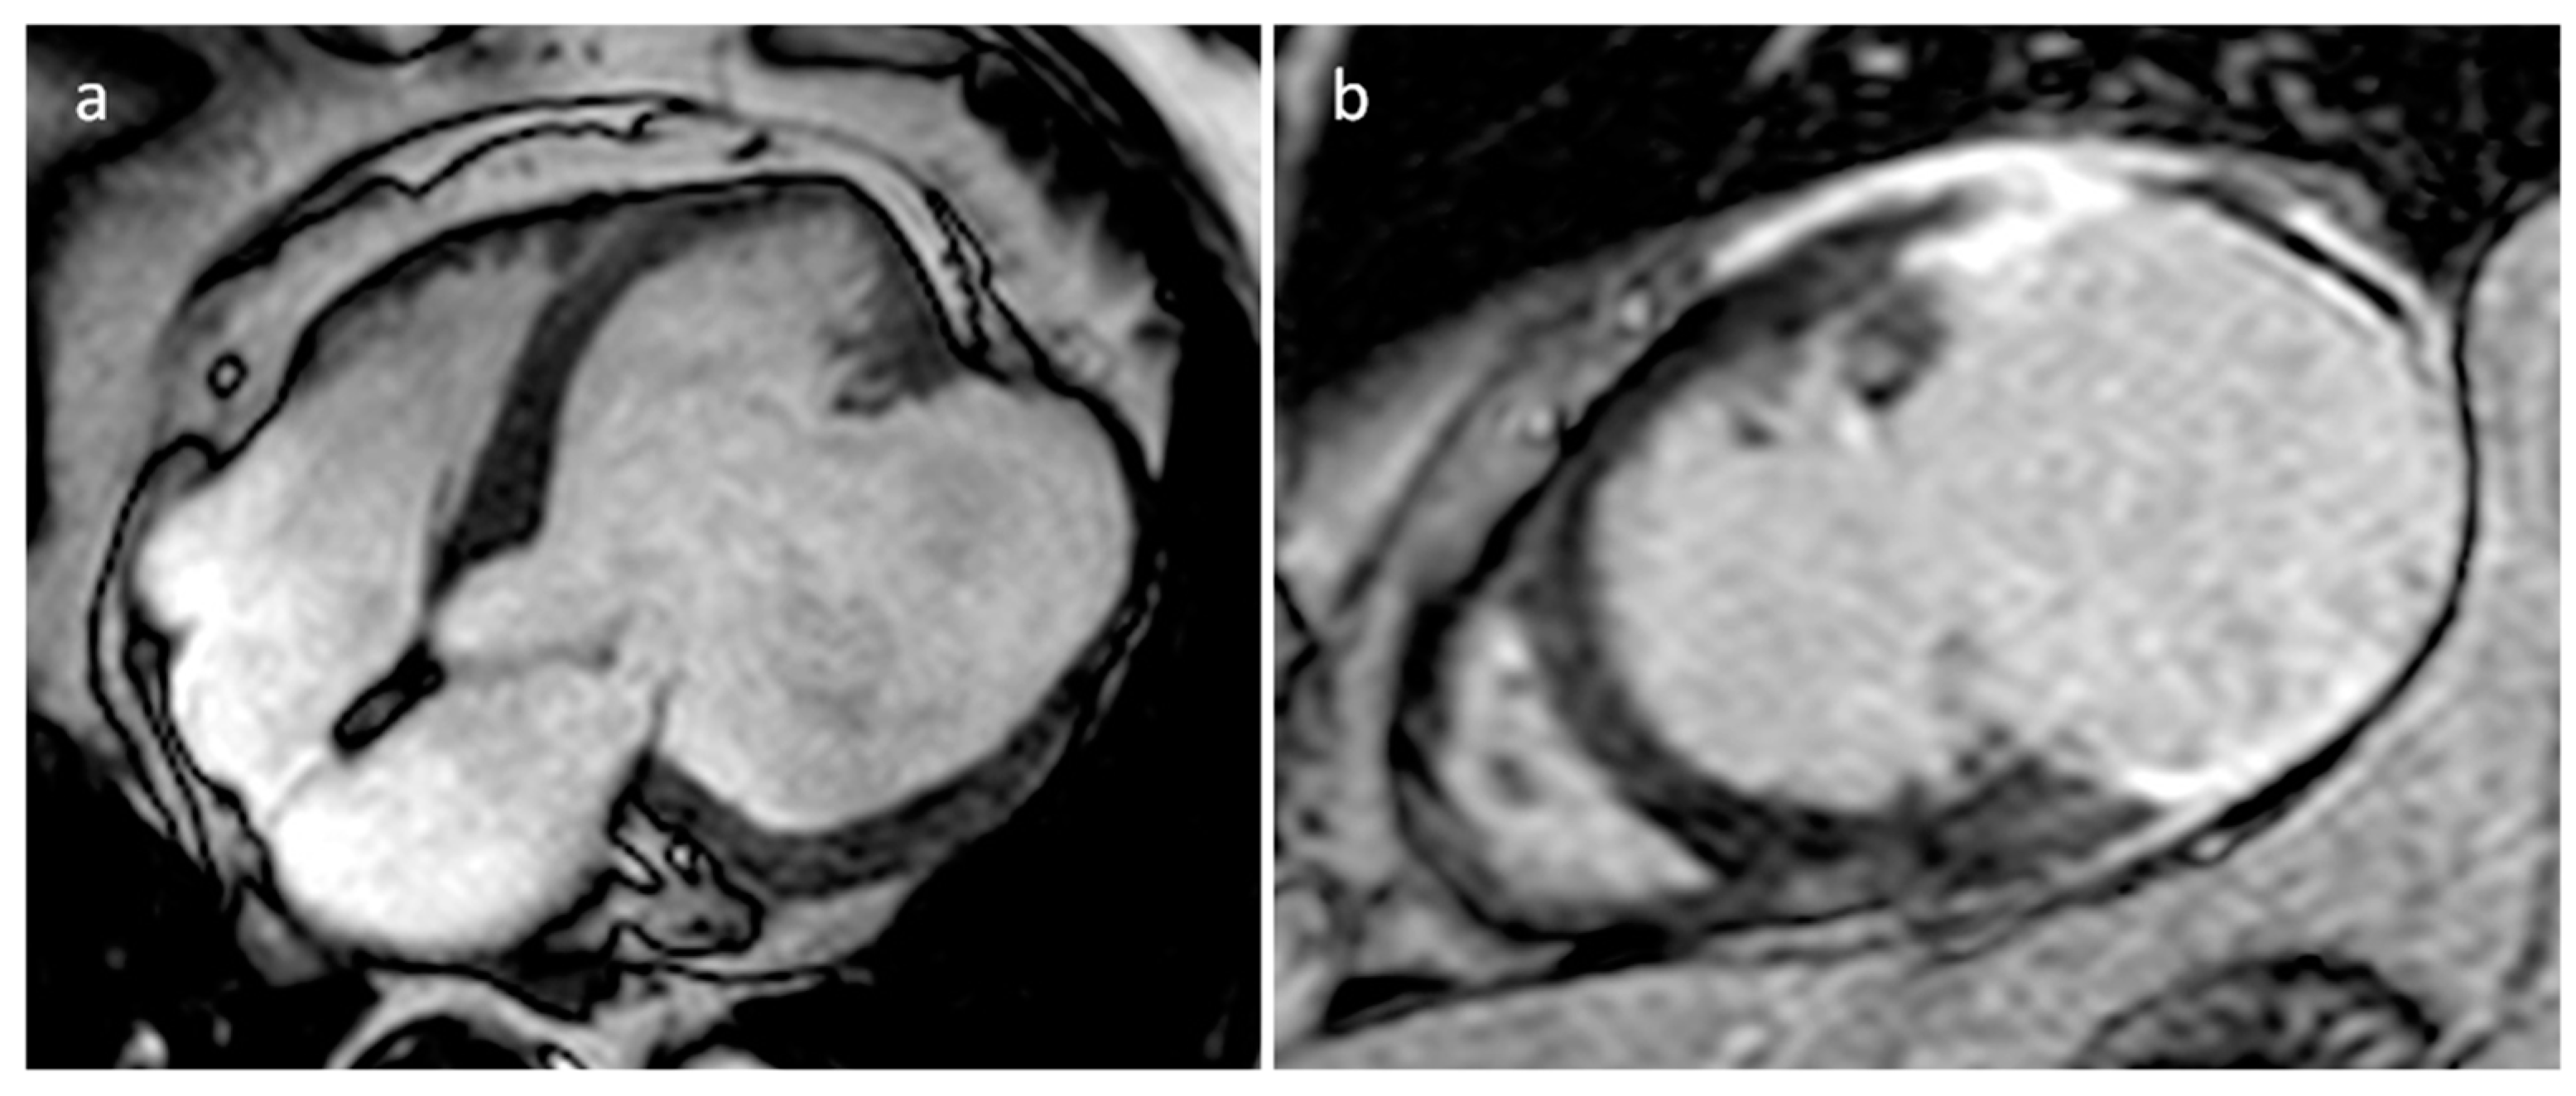

3.11. Echinococcus Cyst

| Echinococcus cyst | Adulthood | Myocardium, pericardium | Usually, asymptomatic | Typical hydatic cyst imaging characteristics | Well defined cystic mass with or without septations | Hypodense lesion with a wall, daughter cysts, peripheral calcifications | Hypo T1w, hyper T2w |